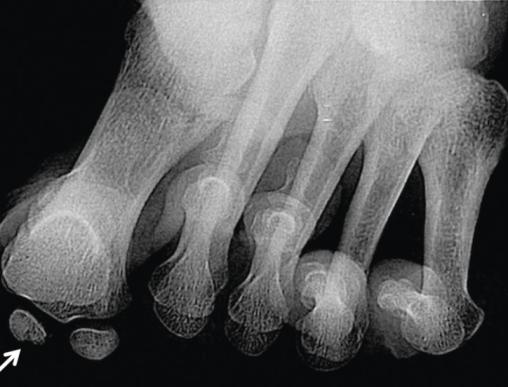

La radiographie avec incidence axiale des sésamoïdes met en évidence un aspect fragmenté et hétérogène du sésamoïde médial (fig. 1 ).

La radiographie avec incidence axiale des sésamoïdes met en évidence un aspect fragmenté et hétérogène du sésamoïde médial (

La radiographie est l’examen de première intention pour les pathologies sésamoïdiennes. Les incidences axiales des sésamoïdes de Walter-Müller (en décharge) ou de Güntz (en charge) permettent de visualiser les sésamoïdes de l’hallux ,à la recherche d’un aspect fragmenté, et d’éliminer les diagnostics différentiels (sésamoïde bipartita, ostéonécrose avasculaire).3